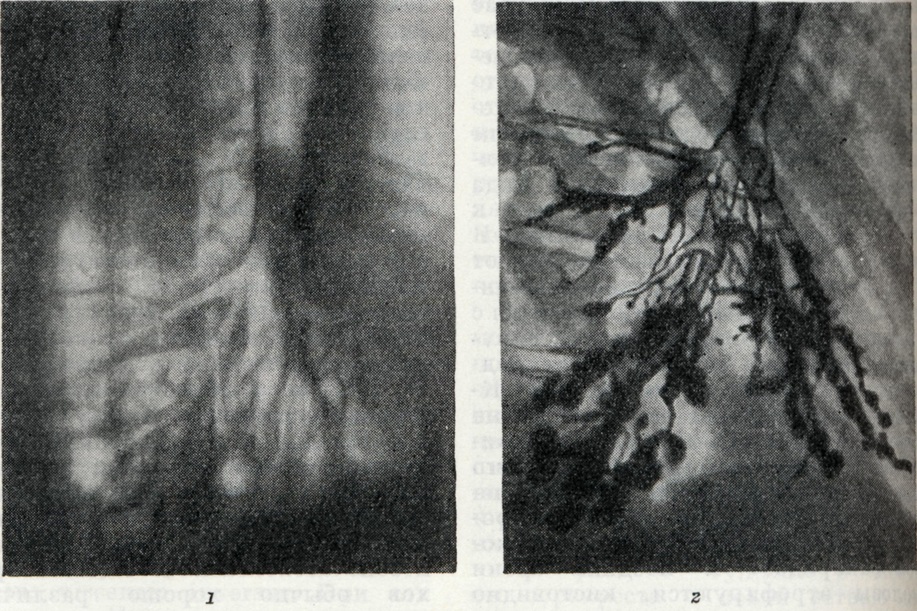

Рентгеноморфологический анализ имеет весьма важное значение в объективной диагностике Б., уточнении их местоположения, распространения, формы и величины. При просвечивании и по обычным рентгенограммам лёгких можно предположить изменения в бронхах по значительному изменению лёгочного рисунка. При цилиндрическом расширении бронхов могут изредка определяться полосовидные просветления и тени, расположенные близко друг к другу и не уменьшающиеся в калибре к периферии. Мешотчатые Б. иногда видны как множественные округлые просветления с плотными стенками, придающие данному участку лёгочного поля своеобразный «сотовый» вид. На томограммах все эти изменения выявляются отчётливее; можно оценить толщину бронхиальных стенок и степень инфильтрации перибронхиальной ткани. Наиболее полно все изменения бронхиального дерева отражаются на бронхограммах (рисунок 1).

Б. вырисовываются на них как стойкие расширения бронхов, при которых диаметр поражённого ствола равен или превышает средний диаметр бронха предыдущего порядка. По форме различают цилиндрические, веретенообразные и мешотчатые Б. (рис. 2). Диаметр цилиндрического Б. больше диаметра дренирующего его бронха не более чем на 15%, диаметр веретенообразного Б.— на 15-30%, диаметр мешотчатого Б.— более чем на 30%. Почти у половины больных Б. одновременно наблюдаются разные формы расширений бронхов. При осложнении процесса абсцедированием на бронхограммах видны одна или несколько бронхоэктатических каверн, сообщающихся с поражёнными бронхами. Последние как бы впадают в полость абсцесса.